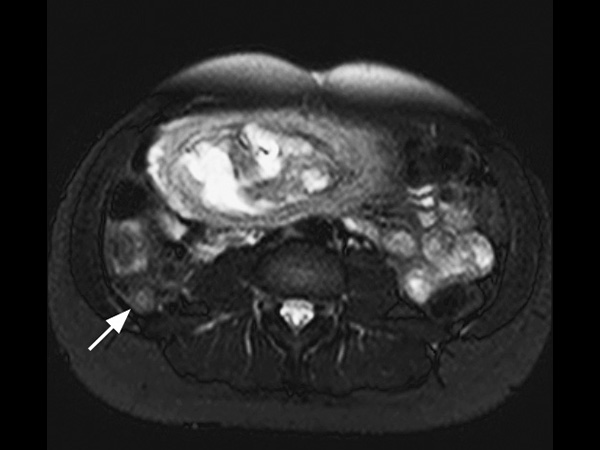

A 25-year-old female, 20 weeks pregnant, presented with right lower quadrant pain. Her white blood cell count was elevated, measuring 14.6. Ultrasound failed to visualize the appendix. Consequently, the patient was referred for MRI. The scan was performed on a 1.5T SmartPath to dStream system using the integrated Posterior coil and the Anterior coil. The exam includes 3-plane T2-weighted scans, 3-plane B-FFE scans and axial T2W SPAIR, all in breath holds < 15 seconds. The MR images demonstrate a distended appendix with adjacent fat stranding. The diagnosis is acute non-perforated retrocecal appendicitis, surgically confirmed. MRI successfully diagnoses appendicitis in pregnancy without using ionizing radiation or contrast. This 18-minute exam without contrast or ionizing radiation has replaced CT in pregnant women at our institution. We have performed over 60 cases in the last 5 years, with 9 positive, surgically confirmed. We saw no false positives, and to the best of our knowledge, no false negatives either. We usually start with ultrasound, but it is frequently negative in these patients. T2-weighted sequences are the mainstay for our diagnosis. With our SmartPath to dStream system, SENSE and dStream allow us to acquire these faster with improved signal. In these patients, who are often short of breath, the scan can be completed in 15 minutes or less.

Axial T2w TSE

Axial SPAIR